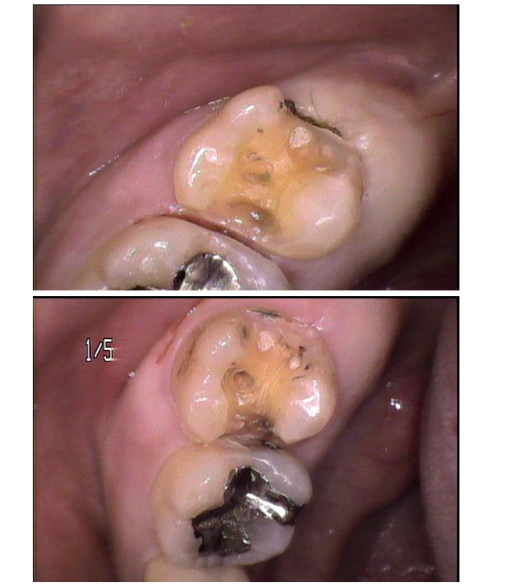

①術後

左上7はう蝕を取り除き1時間でセラミック修復を行った。